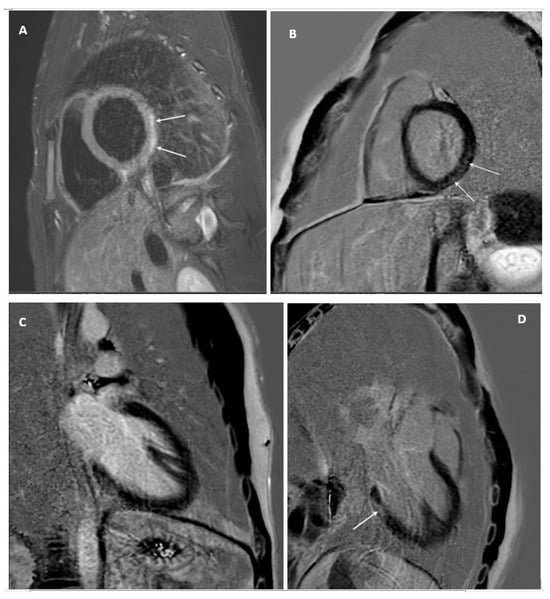

- Belfeki, N.; Zayet, S.; Yassin, M.; Alloujami, M.; Lefoulon, A.; Pezel, T.; Garot, J.; Moini, C. Cardiovascular magnetic resonance imaging pattern in Campylobacter jejuni-related myocarditis. Microorganisms 2022, 10, 208. [Google Scholar] [CrossRef] [PubMed]